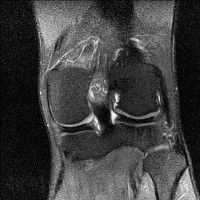

무릎 mri 간단히 봐주실 수 있으시나요 ㅠㅠ

안녕하세요 8년전 십자인대 수술하고 최근 무리한 운동에 무릎 불편감이 생겨서

mri 찍었습니다.

진단결과는 첫 찍은 병원에서 활액막염 이라는 진단을 받았습니다. 혹시 봐주실 수 있으실까요?

올라온 MRI가 단편적이라서 정확한 진단에 어려움이 있지만 십자인대에는 큰 이상이 있지는 않은것 같으며, 무릎관절내 물이 있는 것으로 보아 활액막염의 진단이 맞을 것 같습니다.

하지만 단편적인 영상이기 때문에 촬영병원에서 정확한 판독지 등을 받으시는 것이 좋겠습니다.